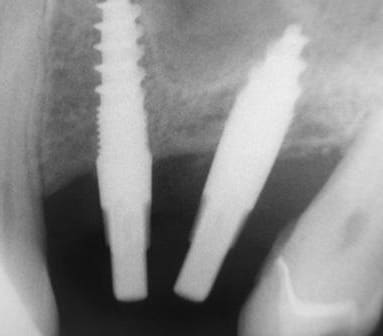

je voulais parler de ce fact pour les implants courts:minimum 4mm os vertical peut suffire (pour eviter un sinus lift externe de tatum) . dans ma pratique depuis quelques années je vois que ca marche , quelques cas cliniques des années passées.

j´ai oublié : 4mm plus 2mm( gagnés par un sinus lift interne)

La forme de ces implants ne me semble pas très adaptée pour soulever la membrane sans la perforer.

Je préfère dans ses cas, avoir un implant dont le bout est plat, et non agressif. Je pense qu'il y a un consensus pour dire que jusqu'à 2mm dans le sinus on risque pas grand chose.